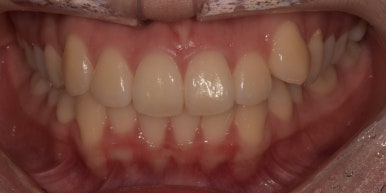

덧니라미네이트 시술 전후

(전) 20241-01-17 (후) 2024-01-24

치료를 마친 모습을 전과 비교해보니 어떤가요?

잇몸라인이 다소 올라가 있는 부분은 어쩔 수 없지만, 앞으로 툭 튀어나와있던 치아가

다른 치아와 유사한 라인으로 맞춰져 더 가지런해 보이죠?

보시면 라미네이트 한 치아와 다른 치아의 색상 또한 큰 차이가 없는 것이 느껴지시죠?

다른 치아들은 모양이나 색상, 배열에 큰 문제가 없었기 때문에

하나의 치아를 라미네이트로 치료하는 저렴한 비용으로 치료를 마무리할 수 있었습니다.